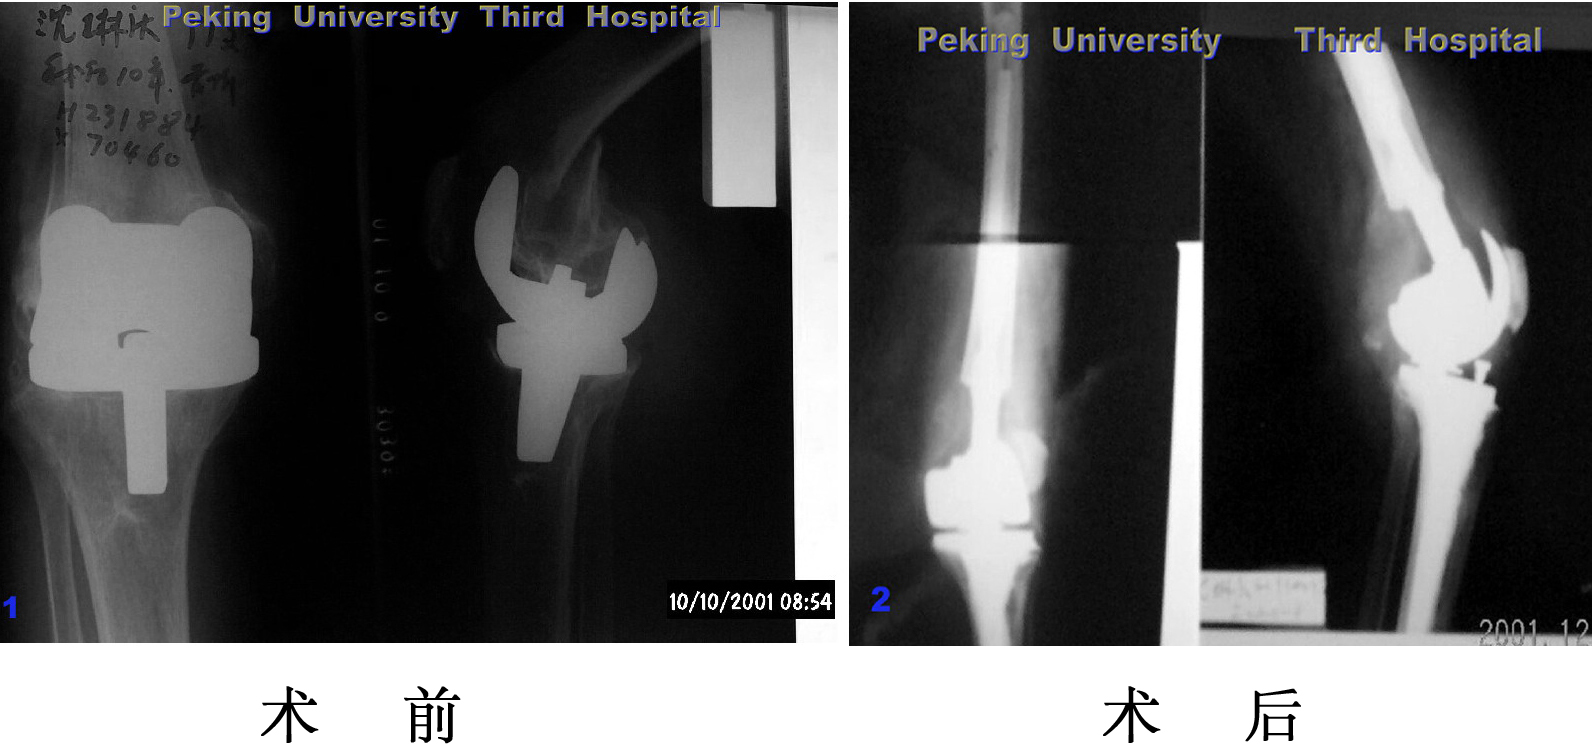

10年前因为膝关节骨性关节炎在我院接受关节置换手术,手术后疼

痛消失功能改善。2001年摔伤导致膝关节周围骨折,再次接受关节置换

手术,患者在病房过了90岁生日。现在关节功能良好,可以自己走路。